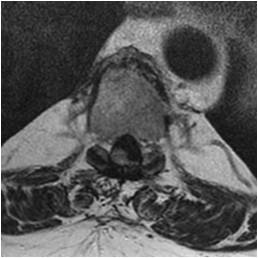

Idiopathic Hypertrophic Pachymeningitis

A chronic progressive diffuse inflammatory fibrosis of the dura mater. Diagnosis of exclusion since meningioma, lymphoma, sarcoid and TBc can present in a similar fashion. MRI findings of low signal intensity mass extending over several levels with linear or nodular peripheral enhancement (representing active inflammation) highly suggestive of the diagnosis. [ Article ]